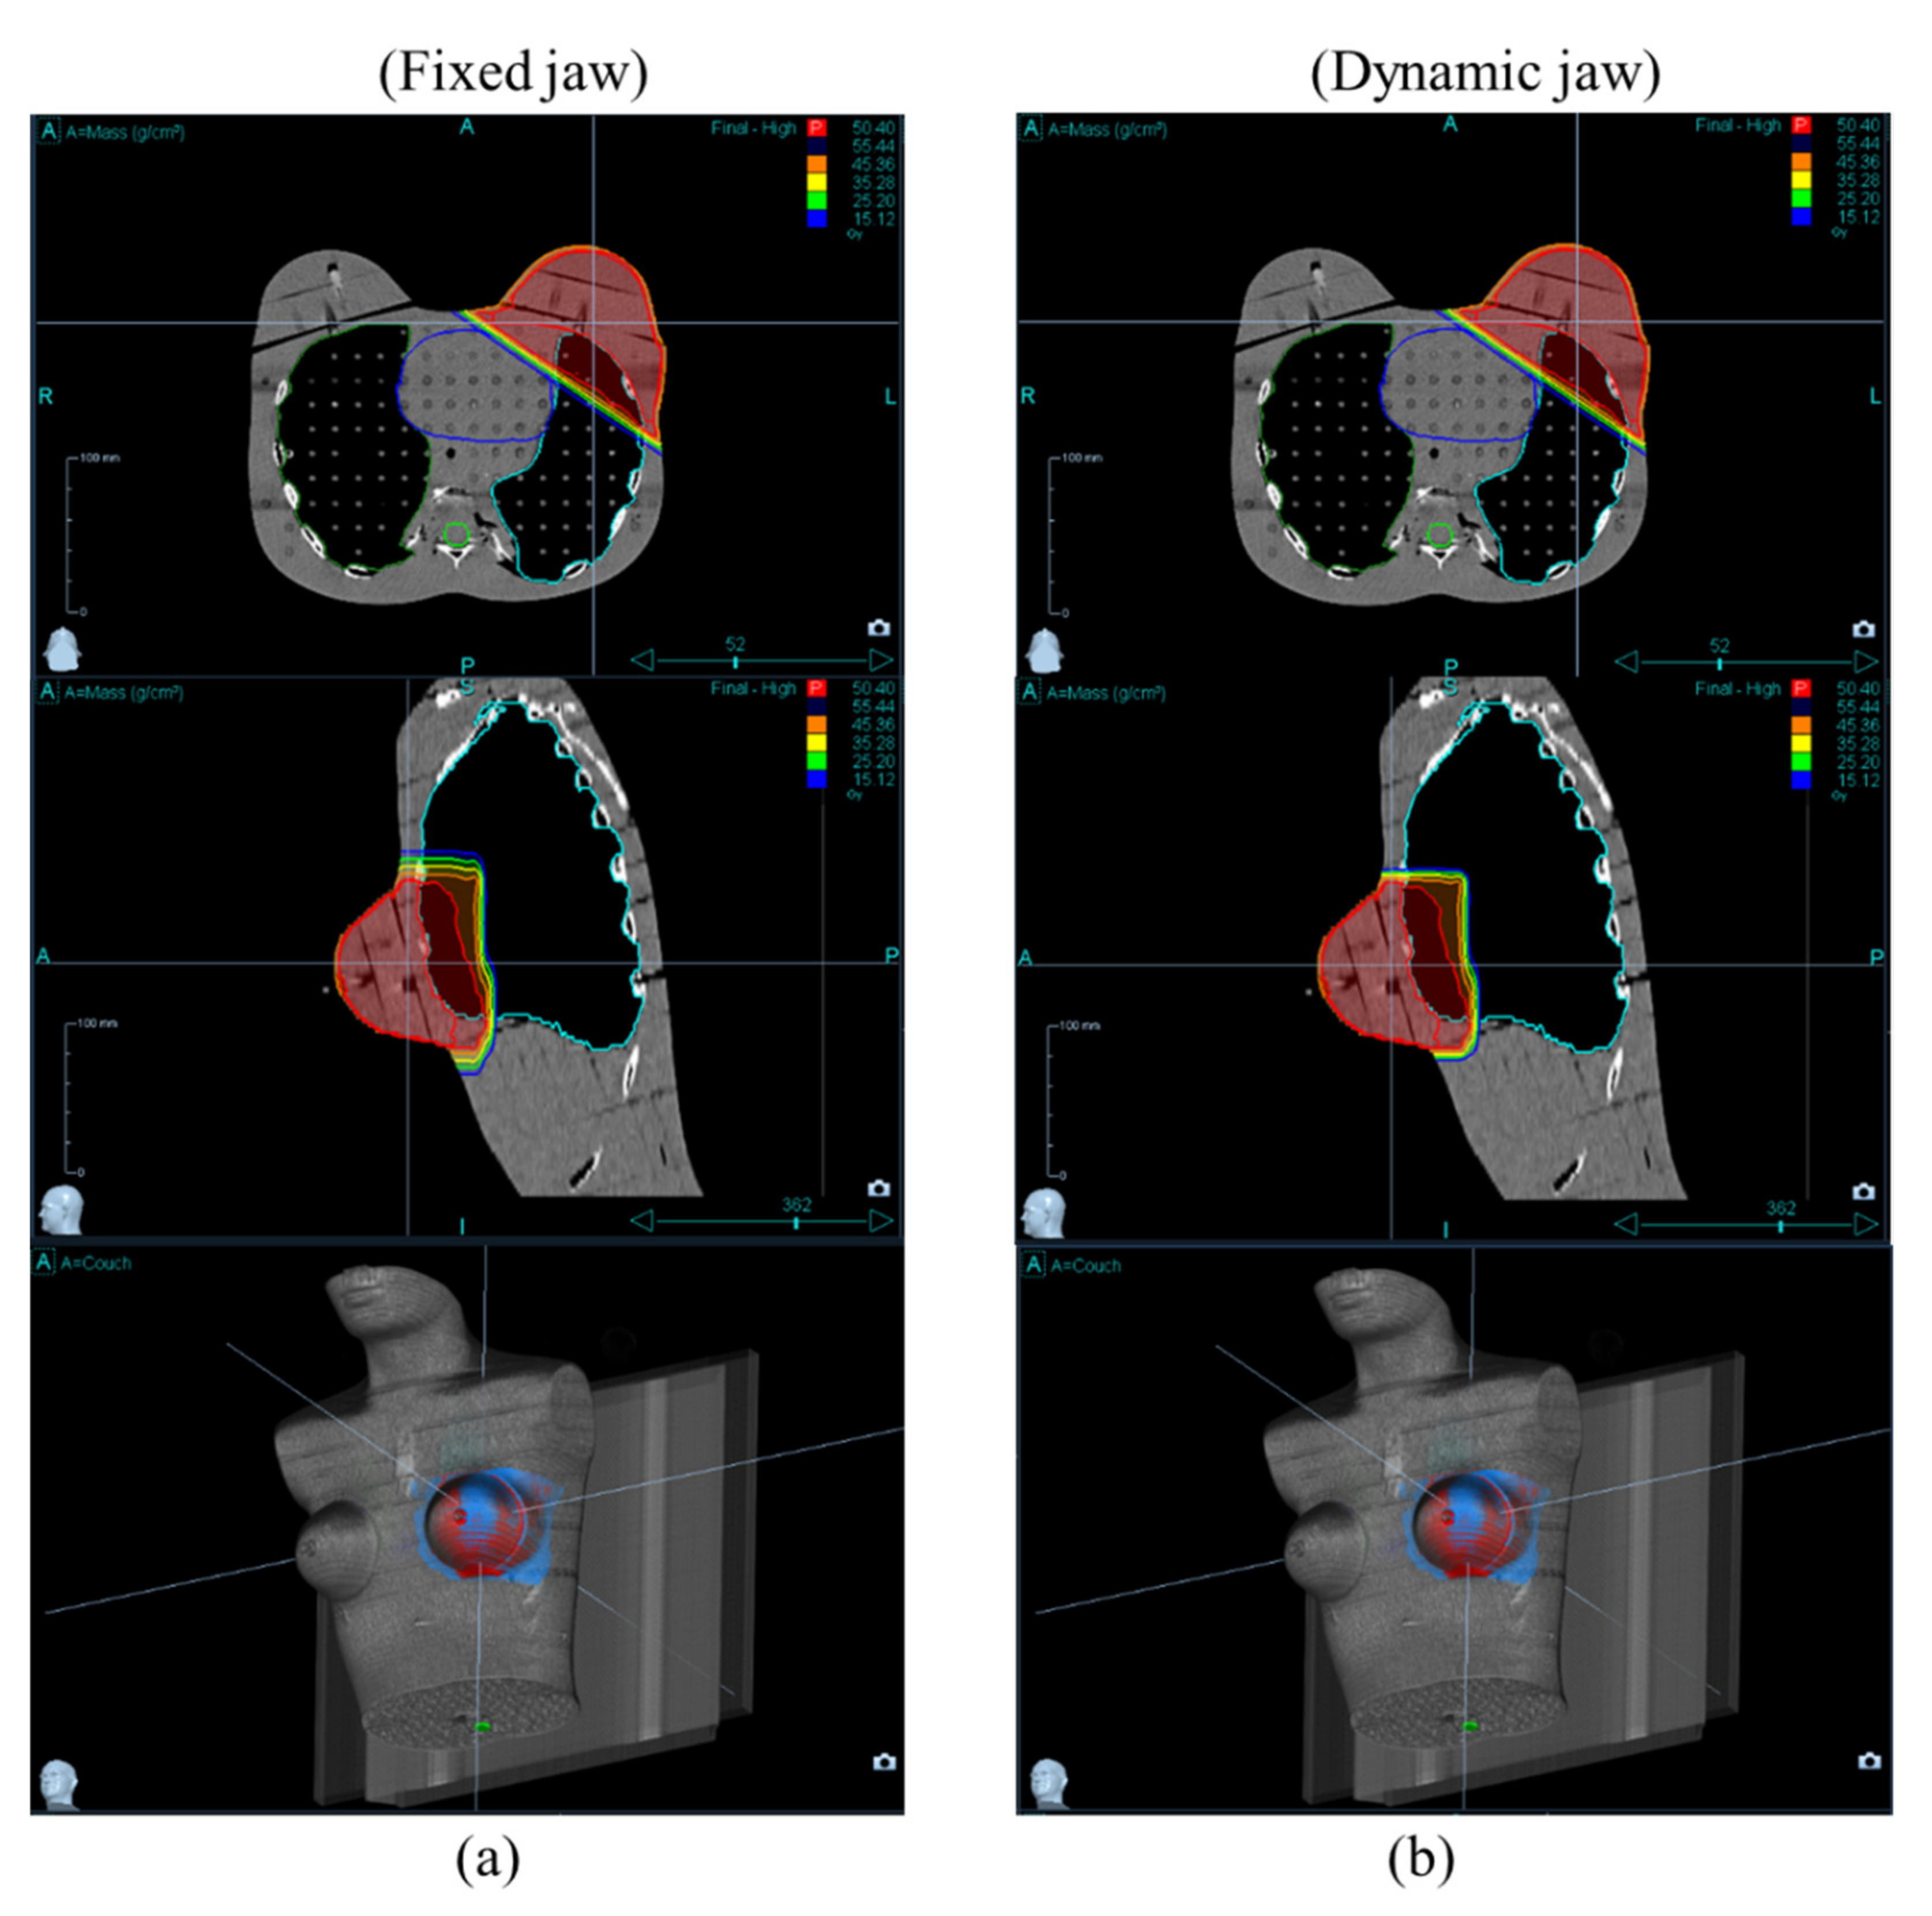

2.2. Treatment Planning

3. Results and Discussion

3.1. Target Coverage